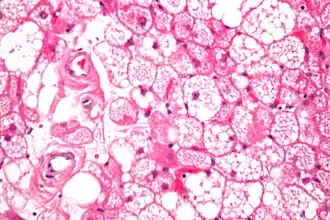

Los tumores se parecen histológicamente a la grasa parda. Se reconocen cuatro tipos histológicos, pero uno es el más frecuente (típico). Se observa un entorno rico en vascularización .

- Tipo lobulillar: grados variables de diferenciación de células uniformes, redondas a ovaladas con células eosinófilicas granulares con bordes prominentes, que se alternan groseramente con adipocitos multivacuolados. Por lo general, hay pequeños núcleos ubicados en el centro sin pleomorfismo. Las células tienen grandes gotas de lípidos citoplasmáticos grandes diseminados por todas partes.[1][2]

- Variante mixoide: matriz basófila suelta, con septos fibrosos gruesos e histiocitos espumosos.

- Variante tipo lipoma: adipocitos univacuolados, con solo células de hibernoma aisladas.

- Variante de células fusiformes: lipoma de células fusiformes combinado con hibernoma.

Hibernoma (aumento intermedio).